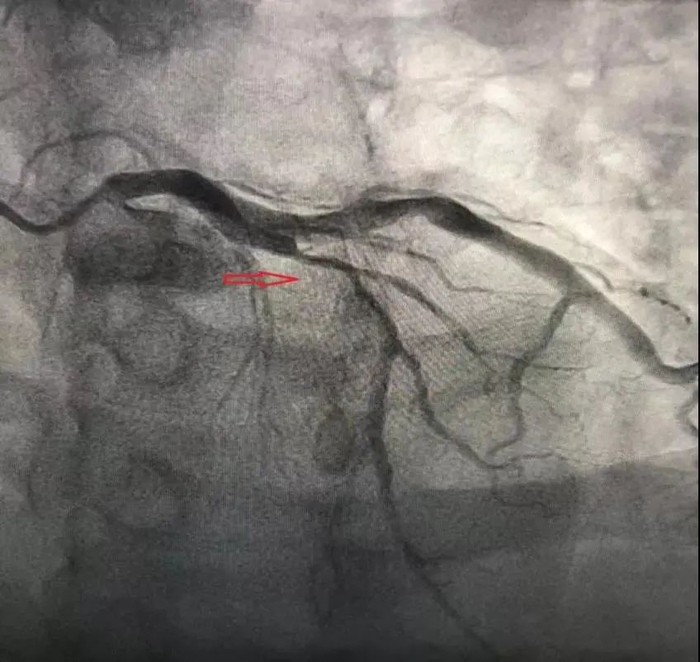

“他还这么年轻,怎么可能有冠心病呢?”李先生的母亲不解说。冠脉造影检查的结果,让所有人出乎意料:李先生的冠脉血管病变十分严重,左前降支堵塞将近80%。而首选的治疗方式,就是置入支架。

近日,随着2枚心脏支架成功置入,李先生的胸闷症状立马消失了。